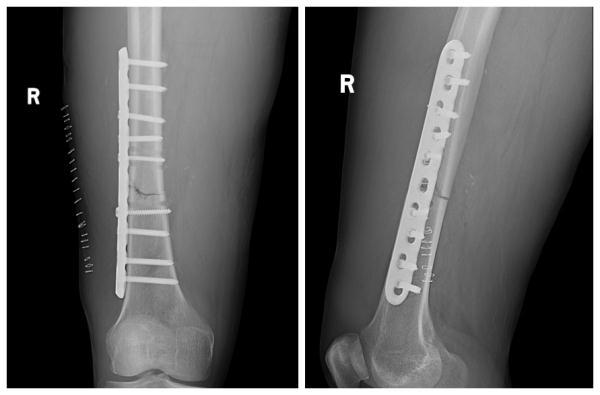

結合術前檢查及綜合評估,創(chuàng)傷組組長姜潼宇、主治醫(yī)生薛澤剛及團隊,針對右股骨干骨折采用右側股骨干骨折切開復位內固定術的微創(chuàng)手術。在右側股骨骨折端取8cm手術切口,放置長達15cm鋼板,骨折端切開插入鋼板,避免的開大刀,微創(chuàng)小切口,減少損傷。通過該微創(chuàng)手術,大大縮短了骨折愈合期,提高了患者的生活質量。目前,秦先生的右下肢已經能夠進行功能康復訓練。